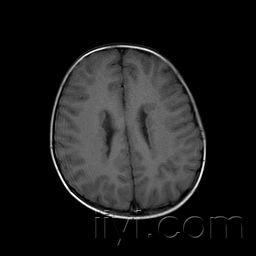

脑灰质异位,脑灰质异位图片

脑灰质异位_人体磁共振成像解

典型病例-脑灰质异位症

脑灰质异位症1例

脑灰质异位

医影学堂丨八个病例带你看懂脑灰质异位的三种类型